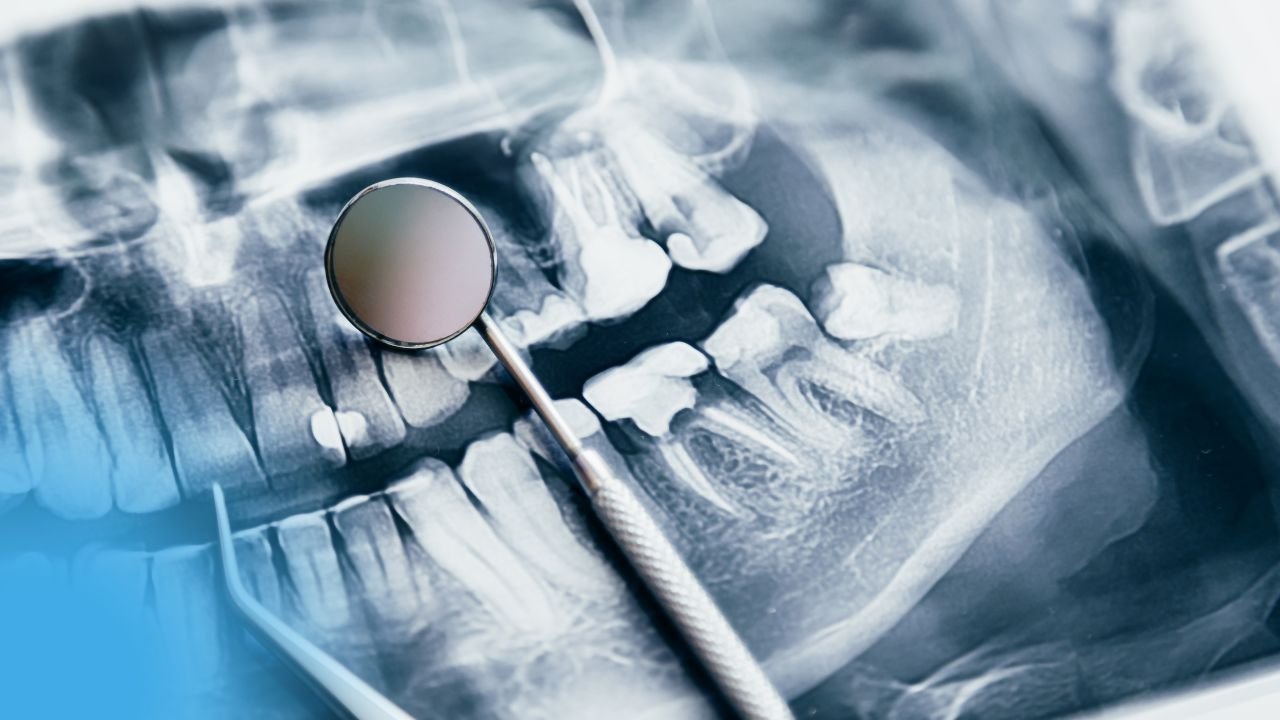

Explorations Radiologiques en Stomatologie / Pathologies Bucco-Dentaires

Explorations Radiologiques en Stomatologie / Pathologies Bucco-Dentaires Introduction En pratique dentaire, l’examen clinique est la pièce angulaire pour l’établissement du...